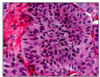

graves disease

obviously hyperfunctioning gland, hyperplasia, and hypertrophy of follicular cells.ar cells